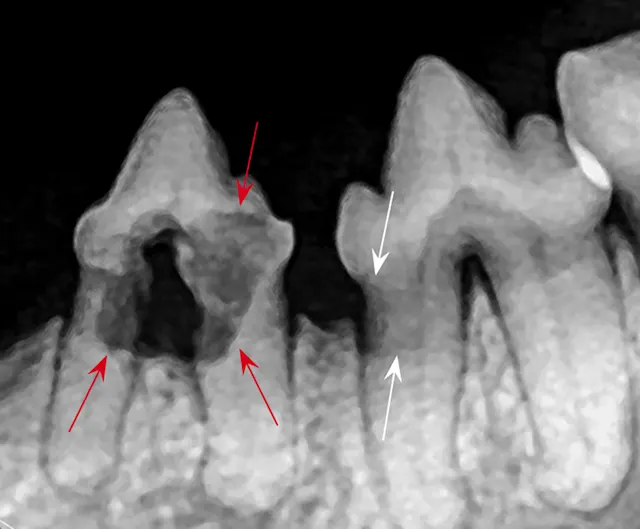

FIGURE 1: Periapical lucency

Periapical lucency develops secondary to bone loss around the tooth root caused by endodontic, neoplastic, or periodontal disease. In this dog, periapical lucency of the maxillary first and second molars (red arrows) developed secondary to periodontal disease. Periapical lucency secondary to endodontic disease (caused by exposure of the pulp from a slab fracture [blue arrow]) is also present surrounding the roots of the right maxillary fourth premolar (white arrow).

Observation of marked mobility of the molars would be expected on anesthetized examination. In this dog, the maxillary fourth premolar would likely not be mobile, as there is still bone surrounding the root apices. Extraction of the maxillary fourth premolar and first and second molars is indicated.